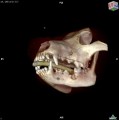

CT - lebka